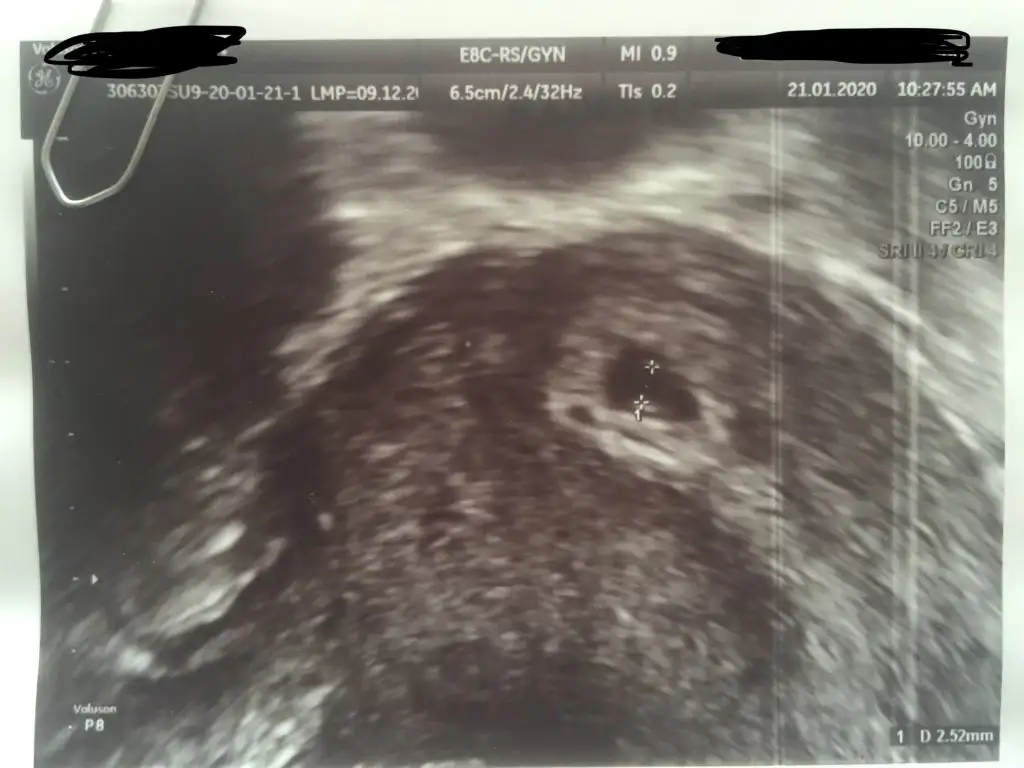

Siz atin bakalim bi ultrason goruntunuzu

Kesenin içinde bişi var gibi sanki ama nasıl görüntü aldıysa artık mantıklı ama hiç düşünmedim ben öyle sağolun yasanırım görüntüyü hiç büyütmeden ölçmüş. yanılma payı yüksek olur tabii. ayrıca yolkun da görünmemesi normal bu durumda. büyütüp bakmıştır elbet diye tahmin ediyorum herşeyin normal olduğunu söylediğine göre...

Olcumu pek iyi yapamamis acikcasi . 6.5 cm yaziyor yukarda o da kese boyutu oluyor sanirim

6,5 cm kese boyuty değil bence çünkü 5mm dedi kese boyutuna 6.5 cmde bebekte görünmesi lazım büyütme oranı fln mı acaba bilemedimOlcumu pek iyi yapamamis acikcasi . 6.5 cm yaziyor yukarda o da kese boyutu oluyor sanirim